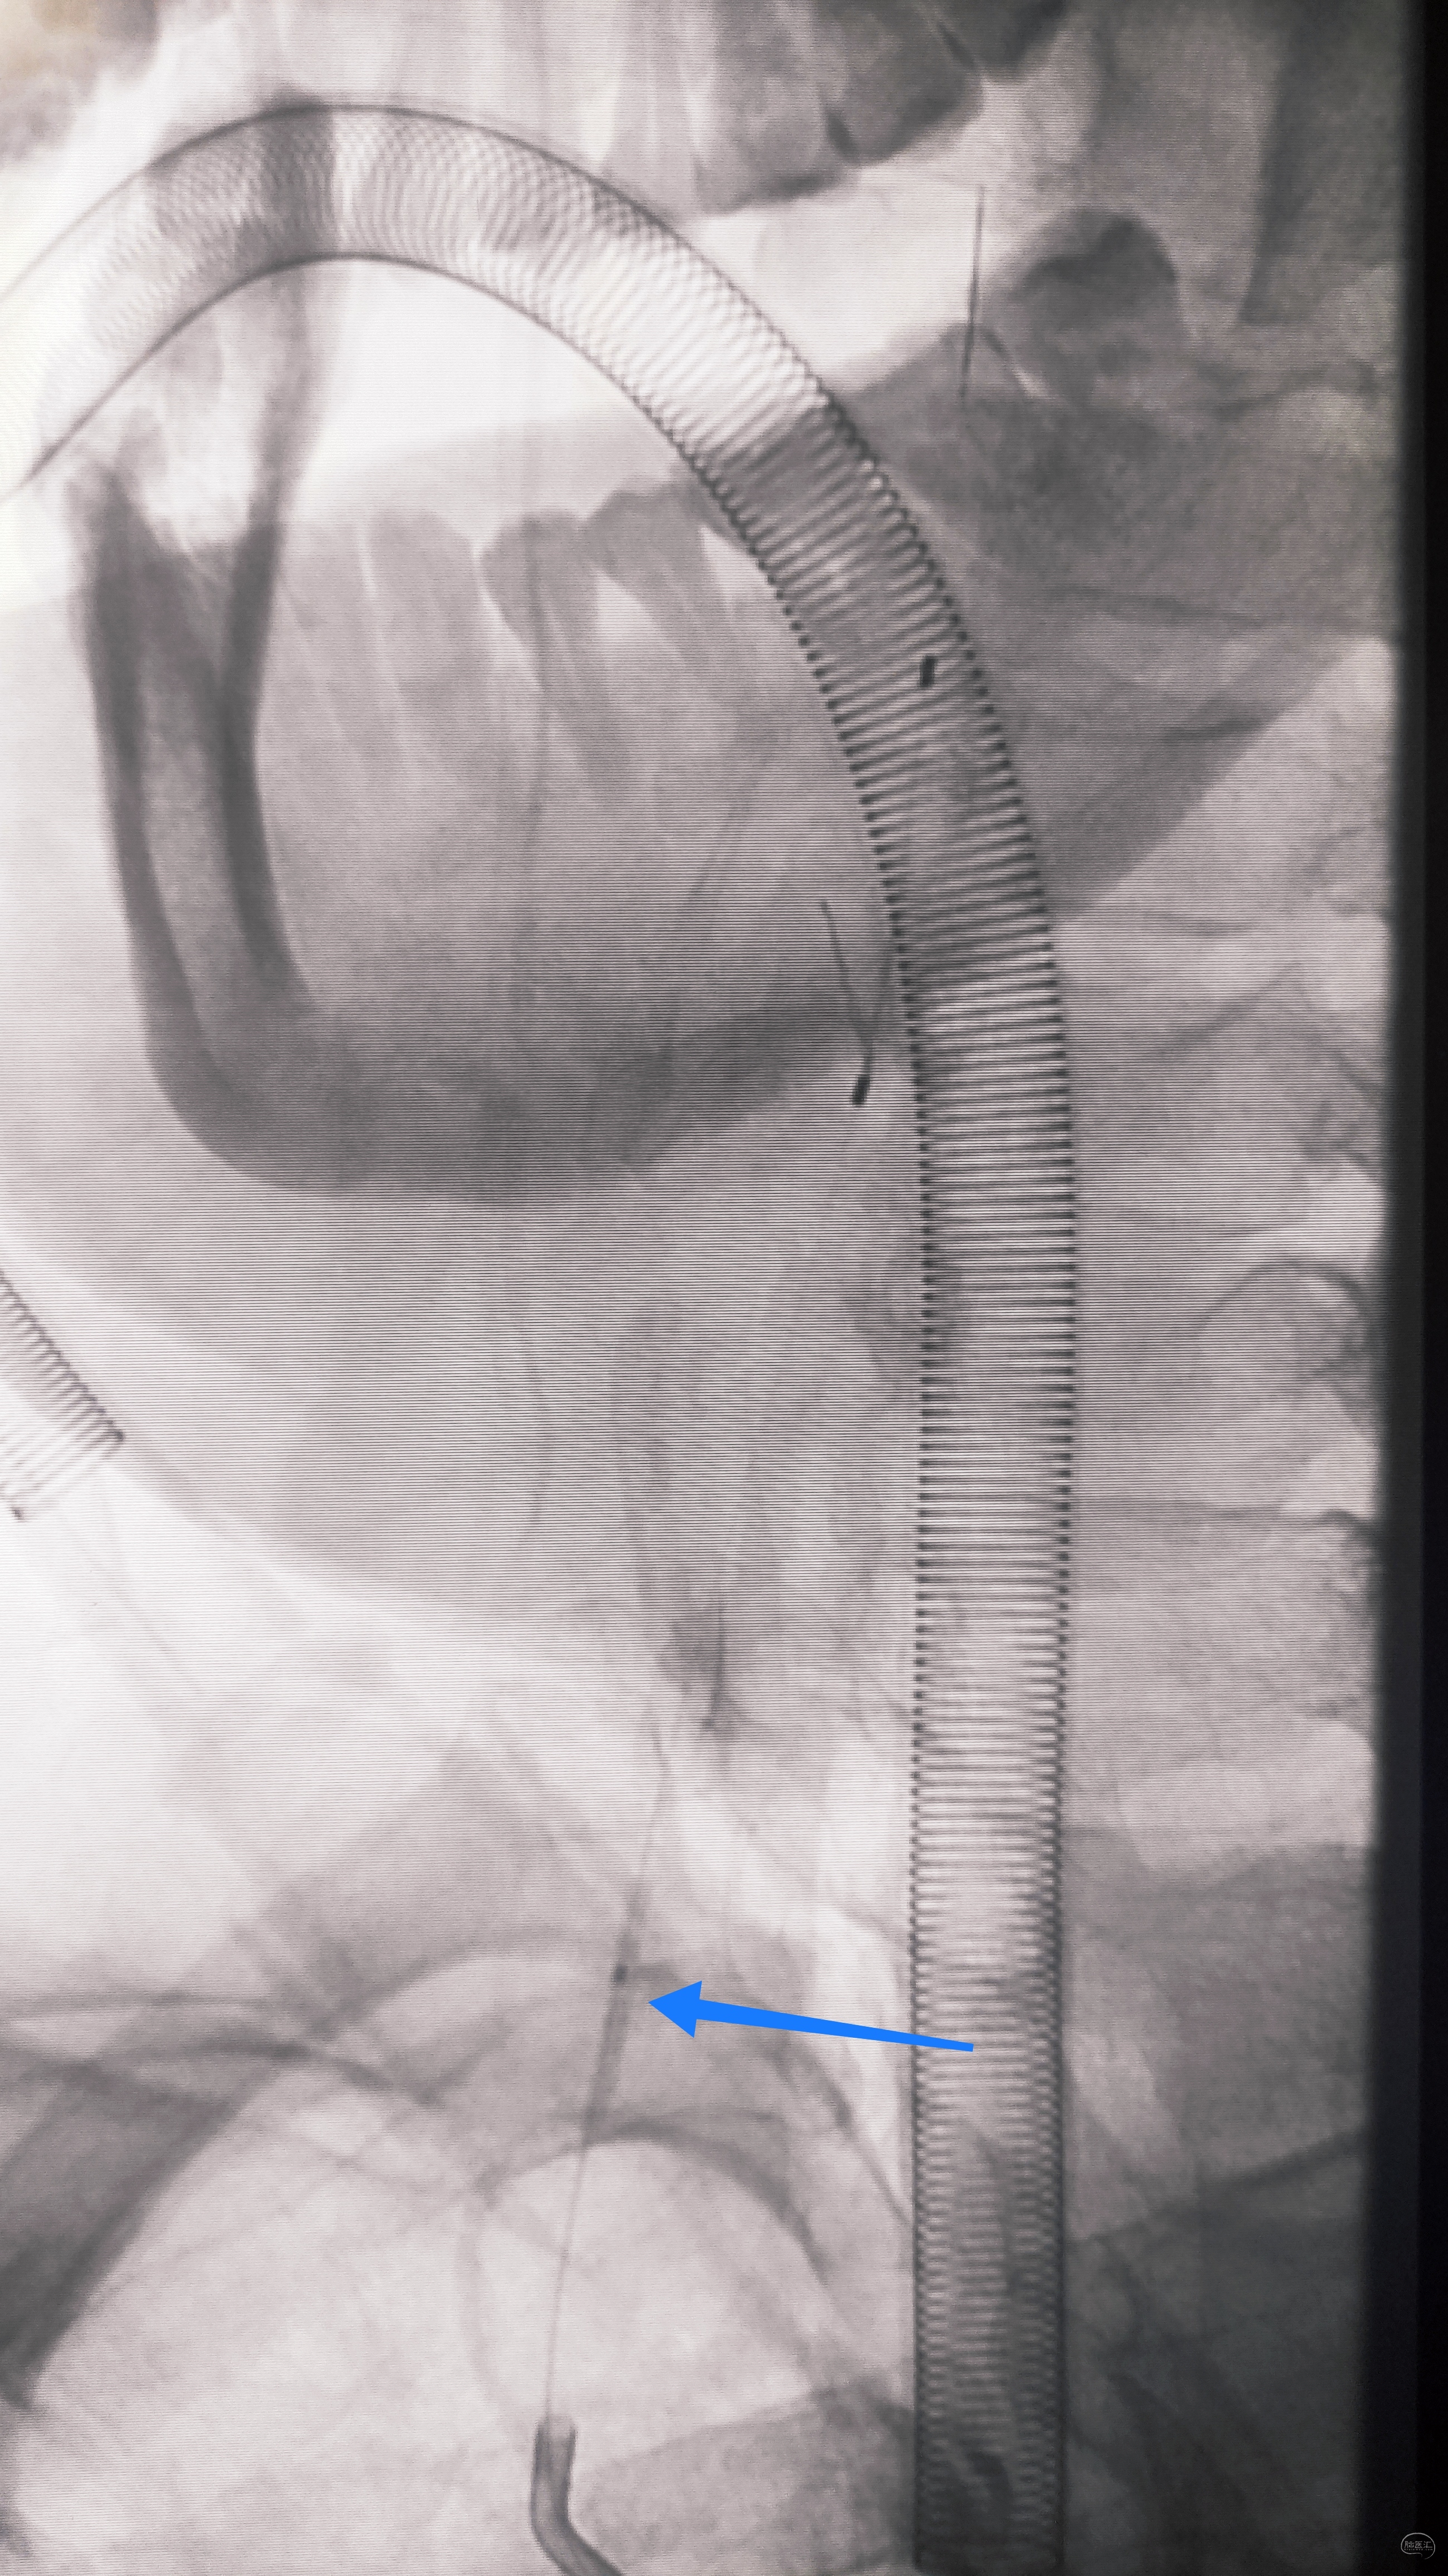

小球囊+大球囊,梯度预扩

一切看似理想,一切看似简单,诡异的事情还是发生了,8F导引导管死活无法进入左侧锁骨下动脉,各种方法尝试个遍:泥鳅走远,单弯挂口,Sim挂口,屡战屡败(水平退步明显,不应该啊,夹层?),因为怕折腾,因为想安全,怕进假腔,弄出夹层。索性换一个思路:空中接力,构建桡-股动脉大环线

自下向上走不通,那就从上边来

经左侧桡动脉6F导引导管,出加长泥鳅,一路向下,逼近右侧股动脉鞘

以为很难,其实不然,泥鳅头段顺利进入股动脉鞘内,但是问题来了,因为是动脉鞘,有活瓣封口,泥鳅无法逆向穿过动脉鞘入口,何解?

那就利用换鞘技术,桡动脉侧持续给泥鳅张力并顶住(助手),缓慢回撤股动脉鞘至体外(主刀),看到泥鳅后抓紧,后拽;长度足够后,带套管重新置入8F股动脉鞘,完成桡-股动脉大环线建立。

泥鳅两段露头,8F导引导管沿泥鳅攀爬,一把干到左侧肱动脉为止

6F导引导管造影确认支架置入部位